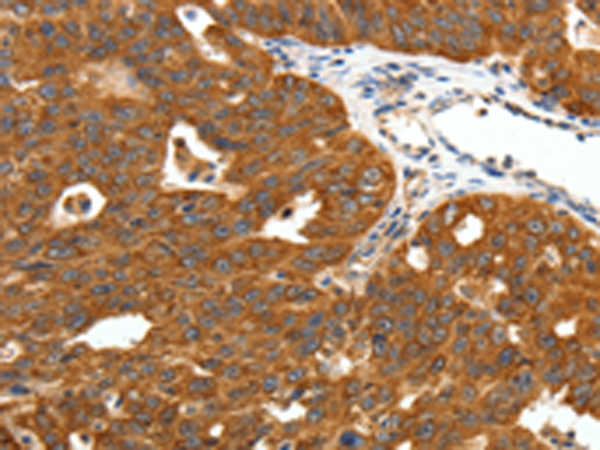

分类: 科研抗体货号: P11340别名:应用: IHC反应种属: Human, Mouse, Rat